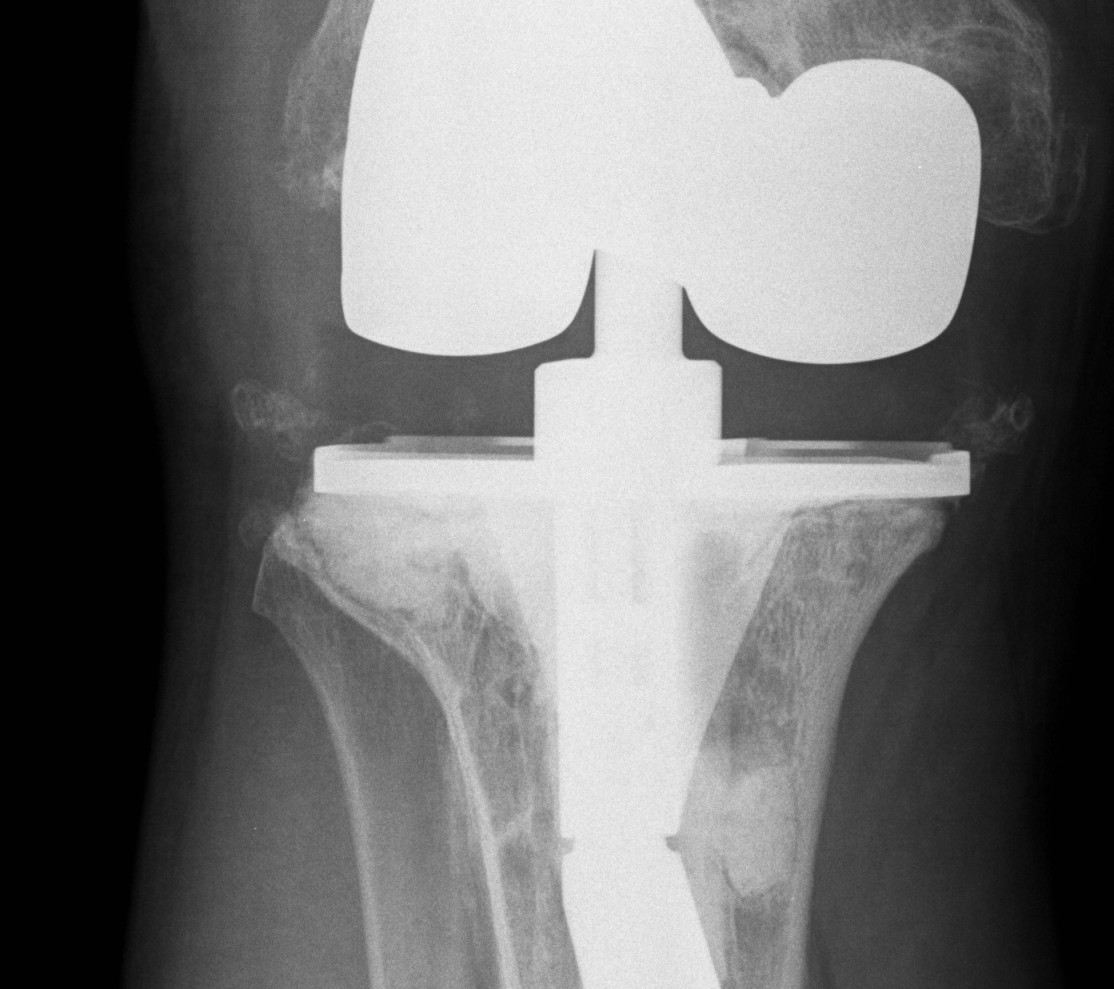

AORI / Andersen Orthopedic Research Institute

T Tibial F Femoral

3. Deficient Metaphysis +/- collaterals +/- extensor mechanism

3. Deficient Metaphysis +/- collaterals / quads

Management

A. Bulk structural allograft

- femoral head

Engh et al JBJS Am 2007

- bulk structure allograft in the tibia in 46 patients followed for 8 years

- 2 deep infections

- average knee society scores 84

- no graft collapse or loosening

B. Tantalum cones metaphyseal filling / Trabecular metal

Meneghini et al JBJS Am 2009

- tantalum porous tibial implant in 15 pateints followed average 3 years

- AORI type 3 and type 2B

- knee society score average 85

- all had evidence osteointegration, no loosening

Howard et al JBJS Am 2011

- femoral tantalum components in 24 knees followed for averag 3 years

- knee society score average 81

- all well fixed with no complications

C. Mesh + impaction bone grafting

D. Tumour prosthesis / Custom implants